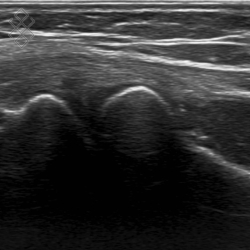

Échographie du Coude

Déroulement

La durée de l'examen est d'environ 20 minutes. Il est indolore et est réalisé par un médecin radiologue.